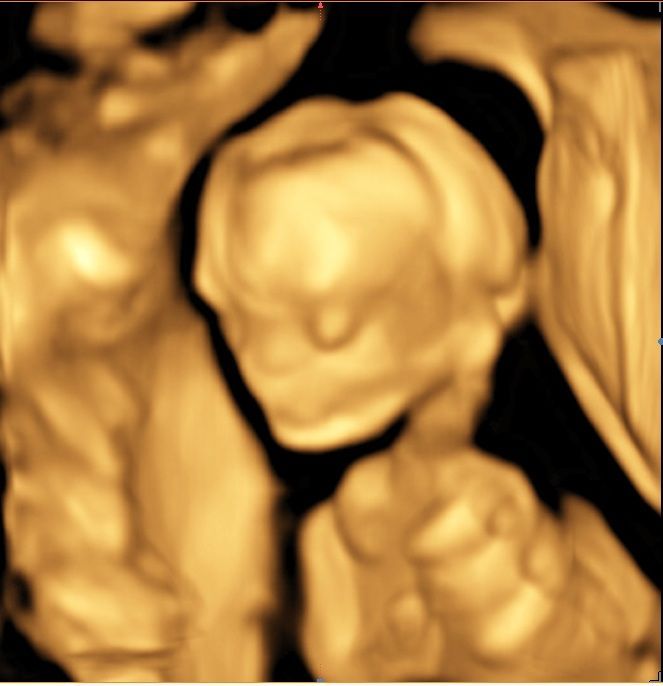

Servicios Ecográficos de Alta Calidad

Realizamos las ecografías de viabilidad del embarazo, genética, morfológica, de bienestar fetal, ecocardiografías fetales, así como procedimientos invasivos como biopsia de vellosidades coriales y amniocentesis.